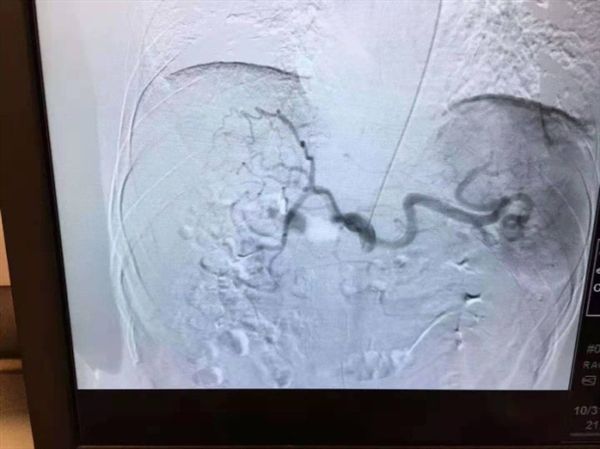

如何解决肝癌介入术后的这个“老大难”问题也成为介入团队的攻关目标之一,团队通过反复查阅文献和与国内外同行的广泛交流学习,发现通过手部的桡动脉穿刺,即可有效解决左某的顾虑。但该途径的穿刺血管很细,穿刺成功率低,最难的地方还在于这种治疗路径与传统治疗路径完全相反,对医生的操作技巧要求极高。为此,介入团队医生们将该手术难点逐一分解攻破并反复演练,于10月31日由游科医师主刀,为左某从桡动脉入路行肝动脉化疗栓塞术,一个半小时后,左某自己走下手术床并步行回到肝胆外科病房,在11月1日出院回家。

桡动脉入路行肝动脉化疗栓塞术这一技术突破,进一步实现了肝癌患者治疗的微创化,充分体现了加速康复外科理念。在重庆市肝胆外科首席专家工作室领衔专家龚建平主任领导下,重医大附二院肝胆外科始终坚持以技术求发展。目前为止,除开展肝癌介入栓塞外,今年介入团队在组长刘作金教授带领下,已成功开展门静脉癌栓放射粒子及支架植入、布—加氏综合征、肝硬化上消化道大出血TIPS治疗、肝癌栓塞分期腹腔镜切除等新技术。

众所周知,肝动脉化疗栓塞术(TACE术)是肝癌治疗的有效、微创手段。其操作原理将导管选择性或超选择性插入到肝脏肿瘤供血靶动脉后,注入适量的栓塞剂,使靶动脉闭塞,从而“饿死”肝肿瘤细胞。手术过程中,医生通过采用注入抗癌药物或药物联合微粒、微球等方式起化疗性栓塞作用,最终达到“杀死”现有肿瘤的效果。

创新的TACE术——经桡动脉入路

通过手部的桡动脉穿刺插管至肝动脉,在目标血管处栓塞、注射栓塞剂。其相较于经股动脉入路,有以下优点: